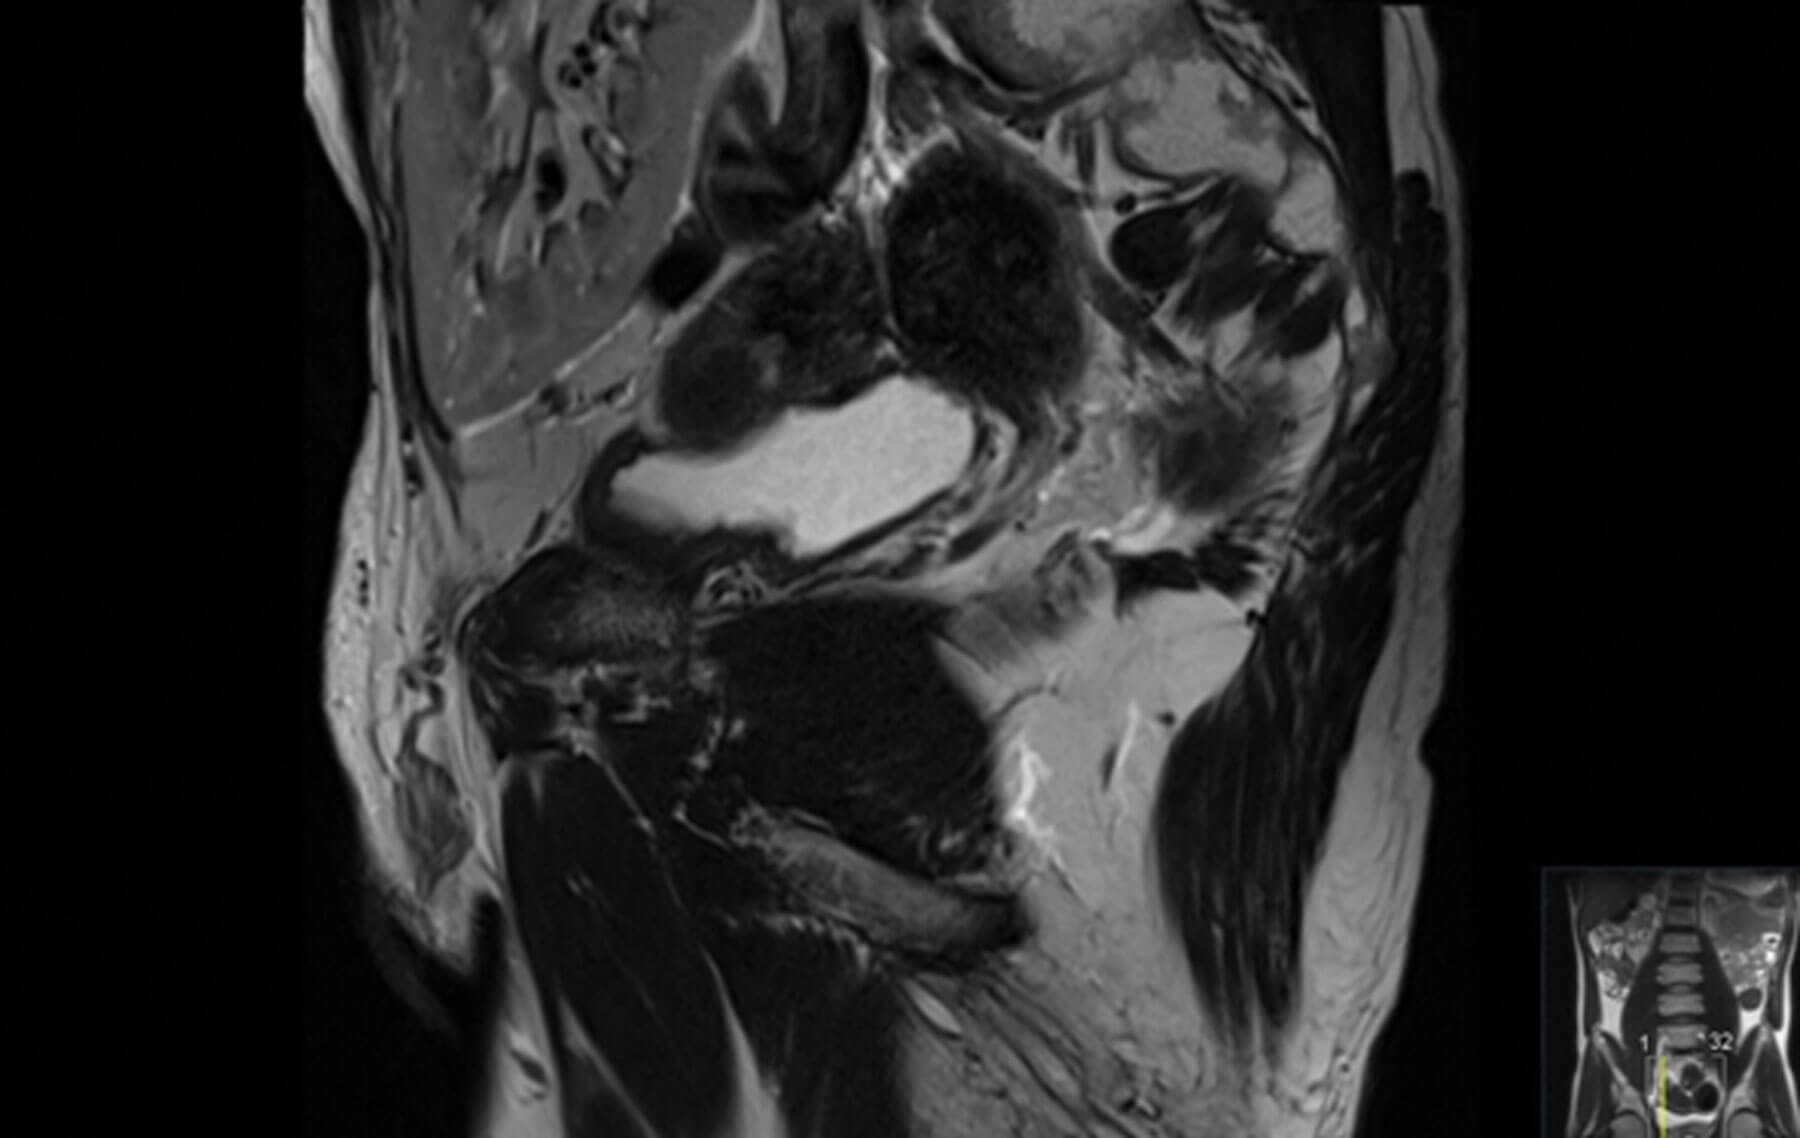

Figure 2: Sagittal image of MRI prostate showing

the proximity of renal transplant to the bladder.

A 55-year-old male had chronic renal failure requiring initial peritoneal dialysis. He had a renal transplant from his partner four years ago. His initial prostate specific antigen (PSA) during the transplant work-up was one. This increased to nine within two years. Another increase in PSA triggered an MRI scan of the prostate which revealed a PI-RADS 5 lesion, T3a in a 20cc prostate. He proceeded to a transperineal prostate biopsy which revealed a Gleason 4+3 cancer with a maximum cancer length of 10mm. Staging prostate specific membrane antigen positron emission tomography (PSMA PET) scan showed no nodal or distant metastasis. He is on regular tacrolimus, anti-hypertensive and insulin. He has a functioning renal transplant.